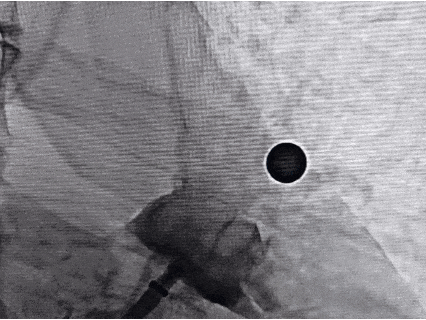

DSA下肝位造影+测量

肝位测量,开口26.13 mm,深度29.65 mm